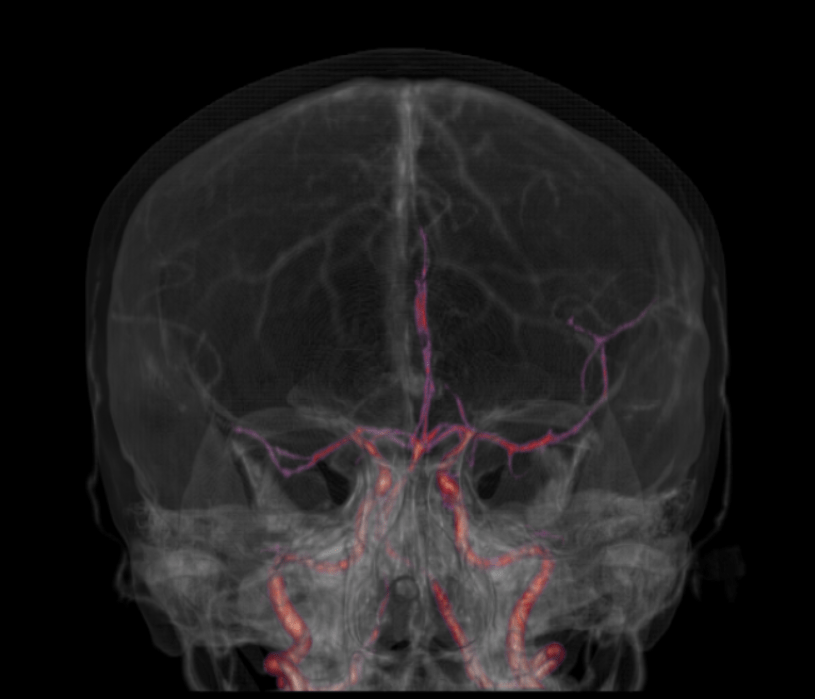

Angio TC cerebral – Algumas Indicações: acidente vascular cerebral (AVC), aneurismas, caracterização de lesões cerebrais.